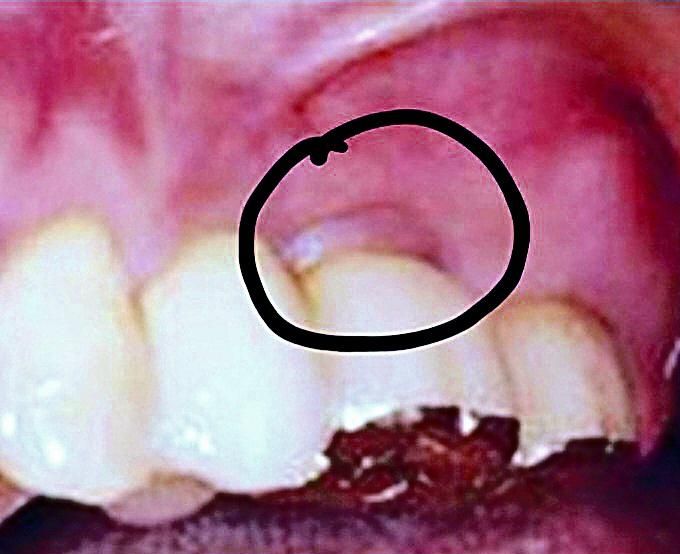

임플란트 후 잇몸밀림(?) / 왜 이런 형태가 되는지 궁금합니다.

임플란트 후 사진처럼 잇몸형태가 매끄럽지 않고 툭 튀어나온 이유가 궁금합니다. 검색해보면 다른 환자분들의 임플란트 후 잇몸형태가 사진처럼 나타나는 경우가 몇몇 보이던데...

왜그런건가요?... 음식물이 더 잘 끼거나 그러지는 않겠죠?..

임플란트를 하고 나면 환자분의 잇몸상태나 임플란트의 위치 또는 보철물의 형태에 따라서 잇몸의 형태가 다르게 보일수 있습니다.

수술을 하고나서 잇몸이 회복되면서 저런 형태로 회복이 되서 그렇습니다. 큰 문제가 잇는건 아니니 너무 걱정하지마세요.

잇몸치유과정에서 간혹 저렇게 과증식 되기도하고, 임플란트 크라운이 잘 안맞이서 잇몸에 지속적으로 자극이 가해져 그럴 수도 있습니다